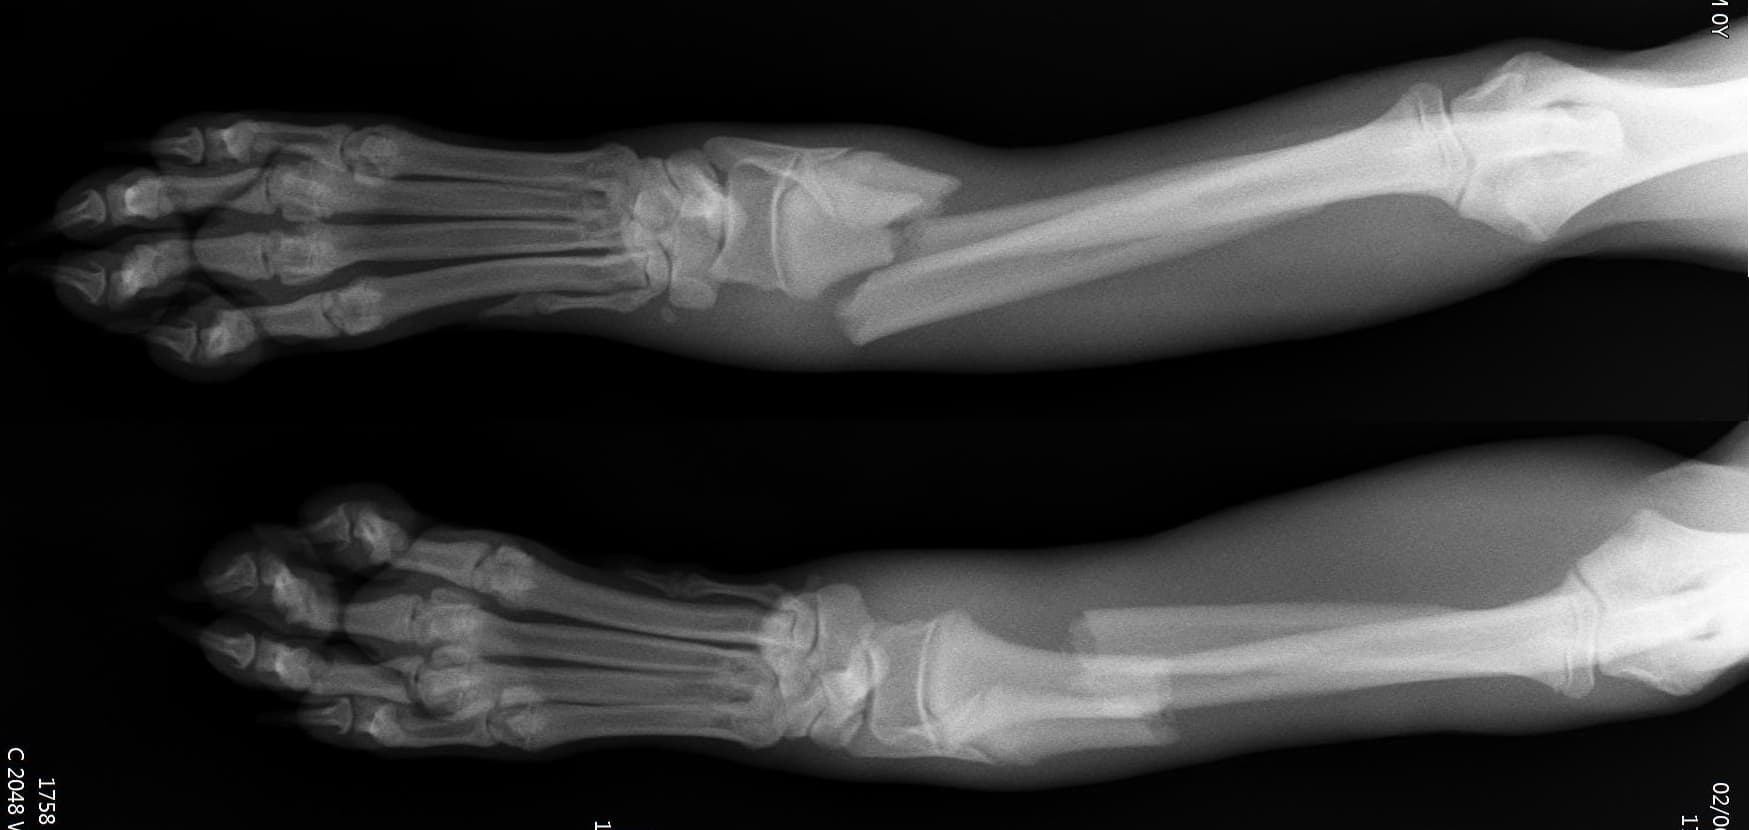

정형외과 전공의 수의사가 직접 수술합니다.

12정교한 정형외과 도구를 사용하여 신속 정확한 정형외과 수술이 가능

13수술 중 골절 상태 혹은 이식물 적용 후 상태 등 육안으로 명확히 확인하기 힘든 상태를 X-ray 확인하여 정확한 수술 결과를 만들어 내는 것이 가능